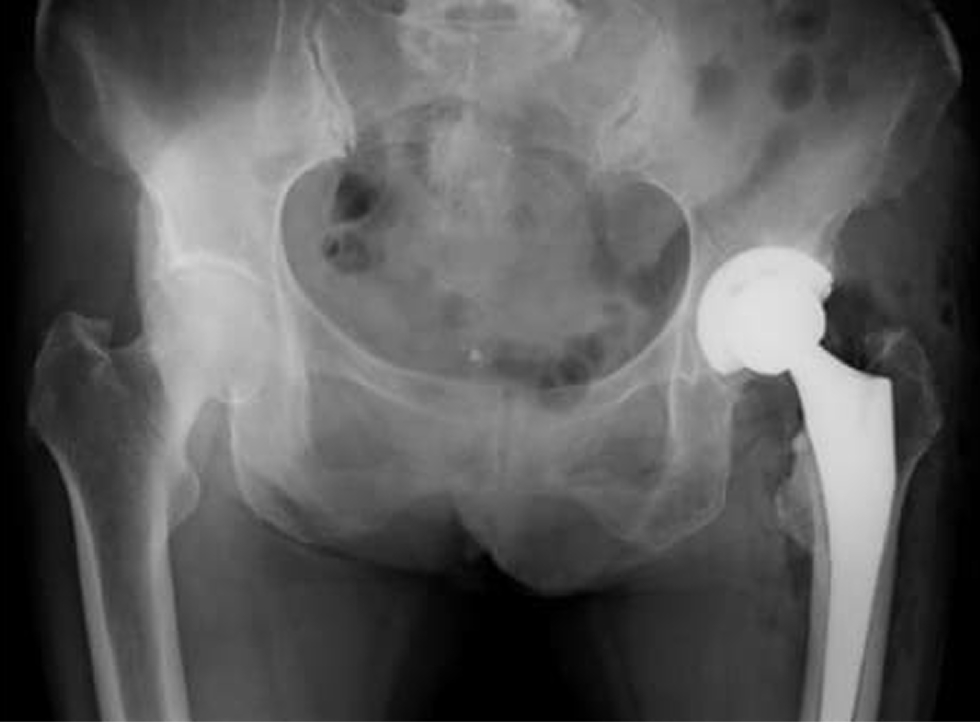

• 変形性股関節症 (術前)

• 術後のレントゲン像